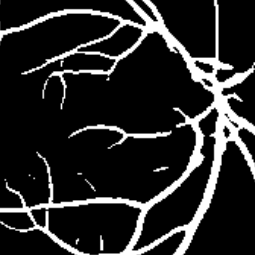

Semantic segmentation of blood vessels is an important task in medical image analysis, but its progress is often hindered by the scarcity of large annotated datasets and the poor generalization of models across different imaging modalities. A key aspect is the tendency of Convolutional Neural Networks (CNNs) to learn texture-based features, which limits their performance when applied to new domains with different visual characteristics. We hypothesize that leveraging geometric priors of vessel shapes, such as their tubular and branching nature, can lead to more robust and data-efficient models. To investigate this, we introduce VessShape, a methodology for generating large-scale 2D synthetic datasets designed to instill a shape bias in segmentation models. VessShape images contain procedurally generated tubular geometries combined with a wide variety of foreground and background textures, encouraging models to learn shape cues rather than textures. We demonstrate that a model pre-trained on VessShape images achieves strong few-shot segmentation performance on two real-world datasets from different domains, requiring only four to ten samples for fine-tuning. Furthermore, the model exhibits notable zero-shot capabilities, effectively segmenting vessels in unseen domains without any target-specific training. Our results indicate that pre-training with a strong shape bias can be an effective strategy to overcome data scarcity and improve model generalization in blood vessel segmentation.